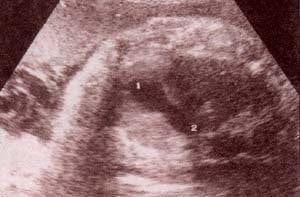

| fig 34. – (a).vasos intratorácicos. cayado aórtico (1). aorta descendente (2). vena cava (3). | fig. 34.– (b). cayado aórtico (1).vasos del cuello. carótida (2). |